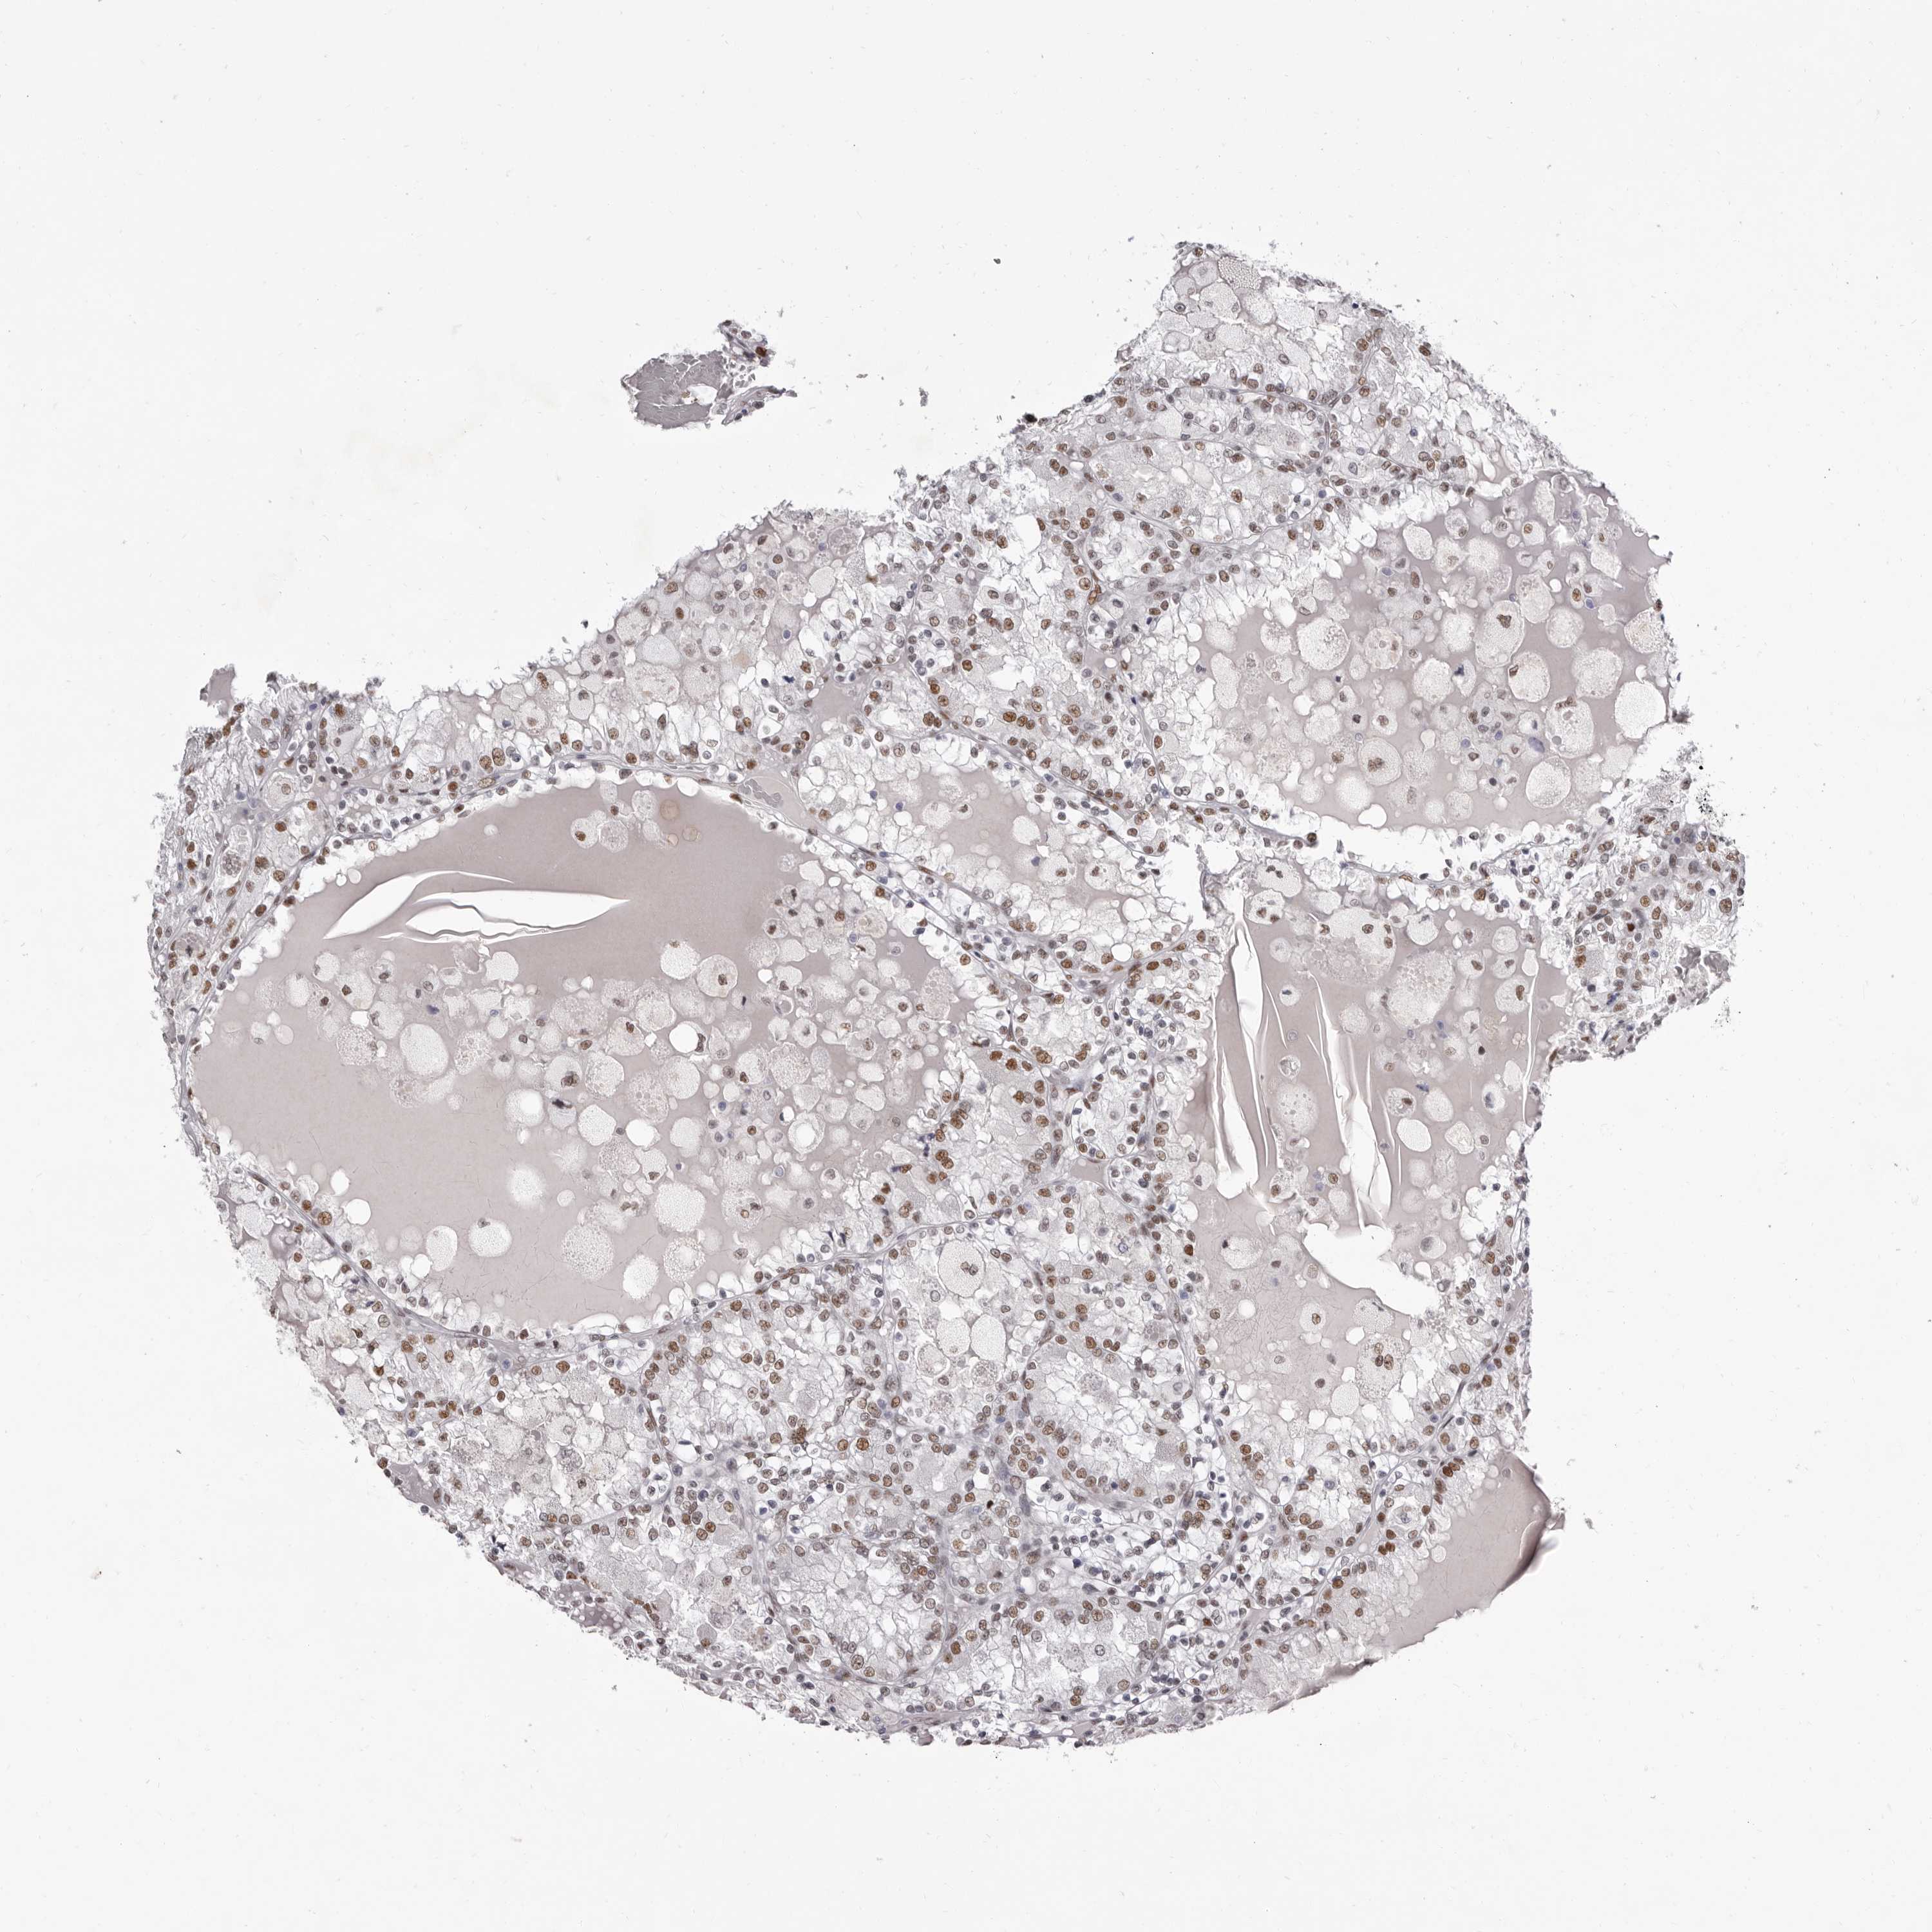

CANCER RENAL CANCER Show tissue menu

KICH TCGA KIRC TCGA KIRC VALIDATION KIRP TCGA PROTEIN RCC CPTAC PROTEIN EXPRESSION